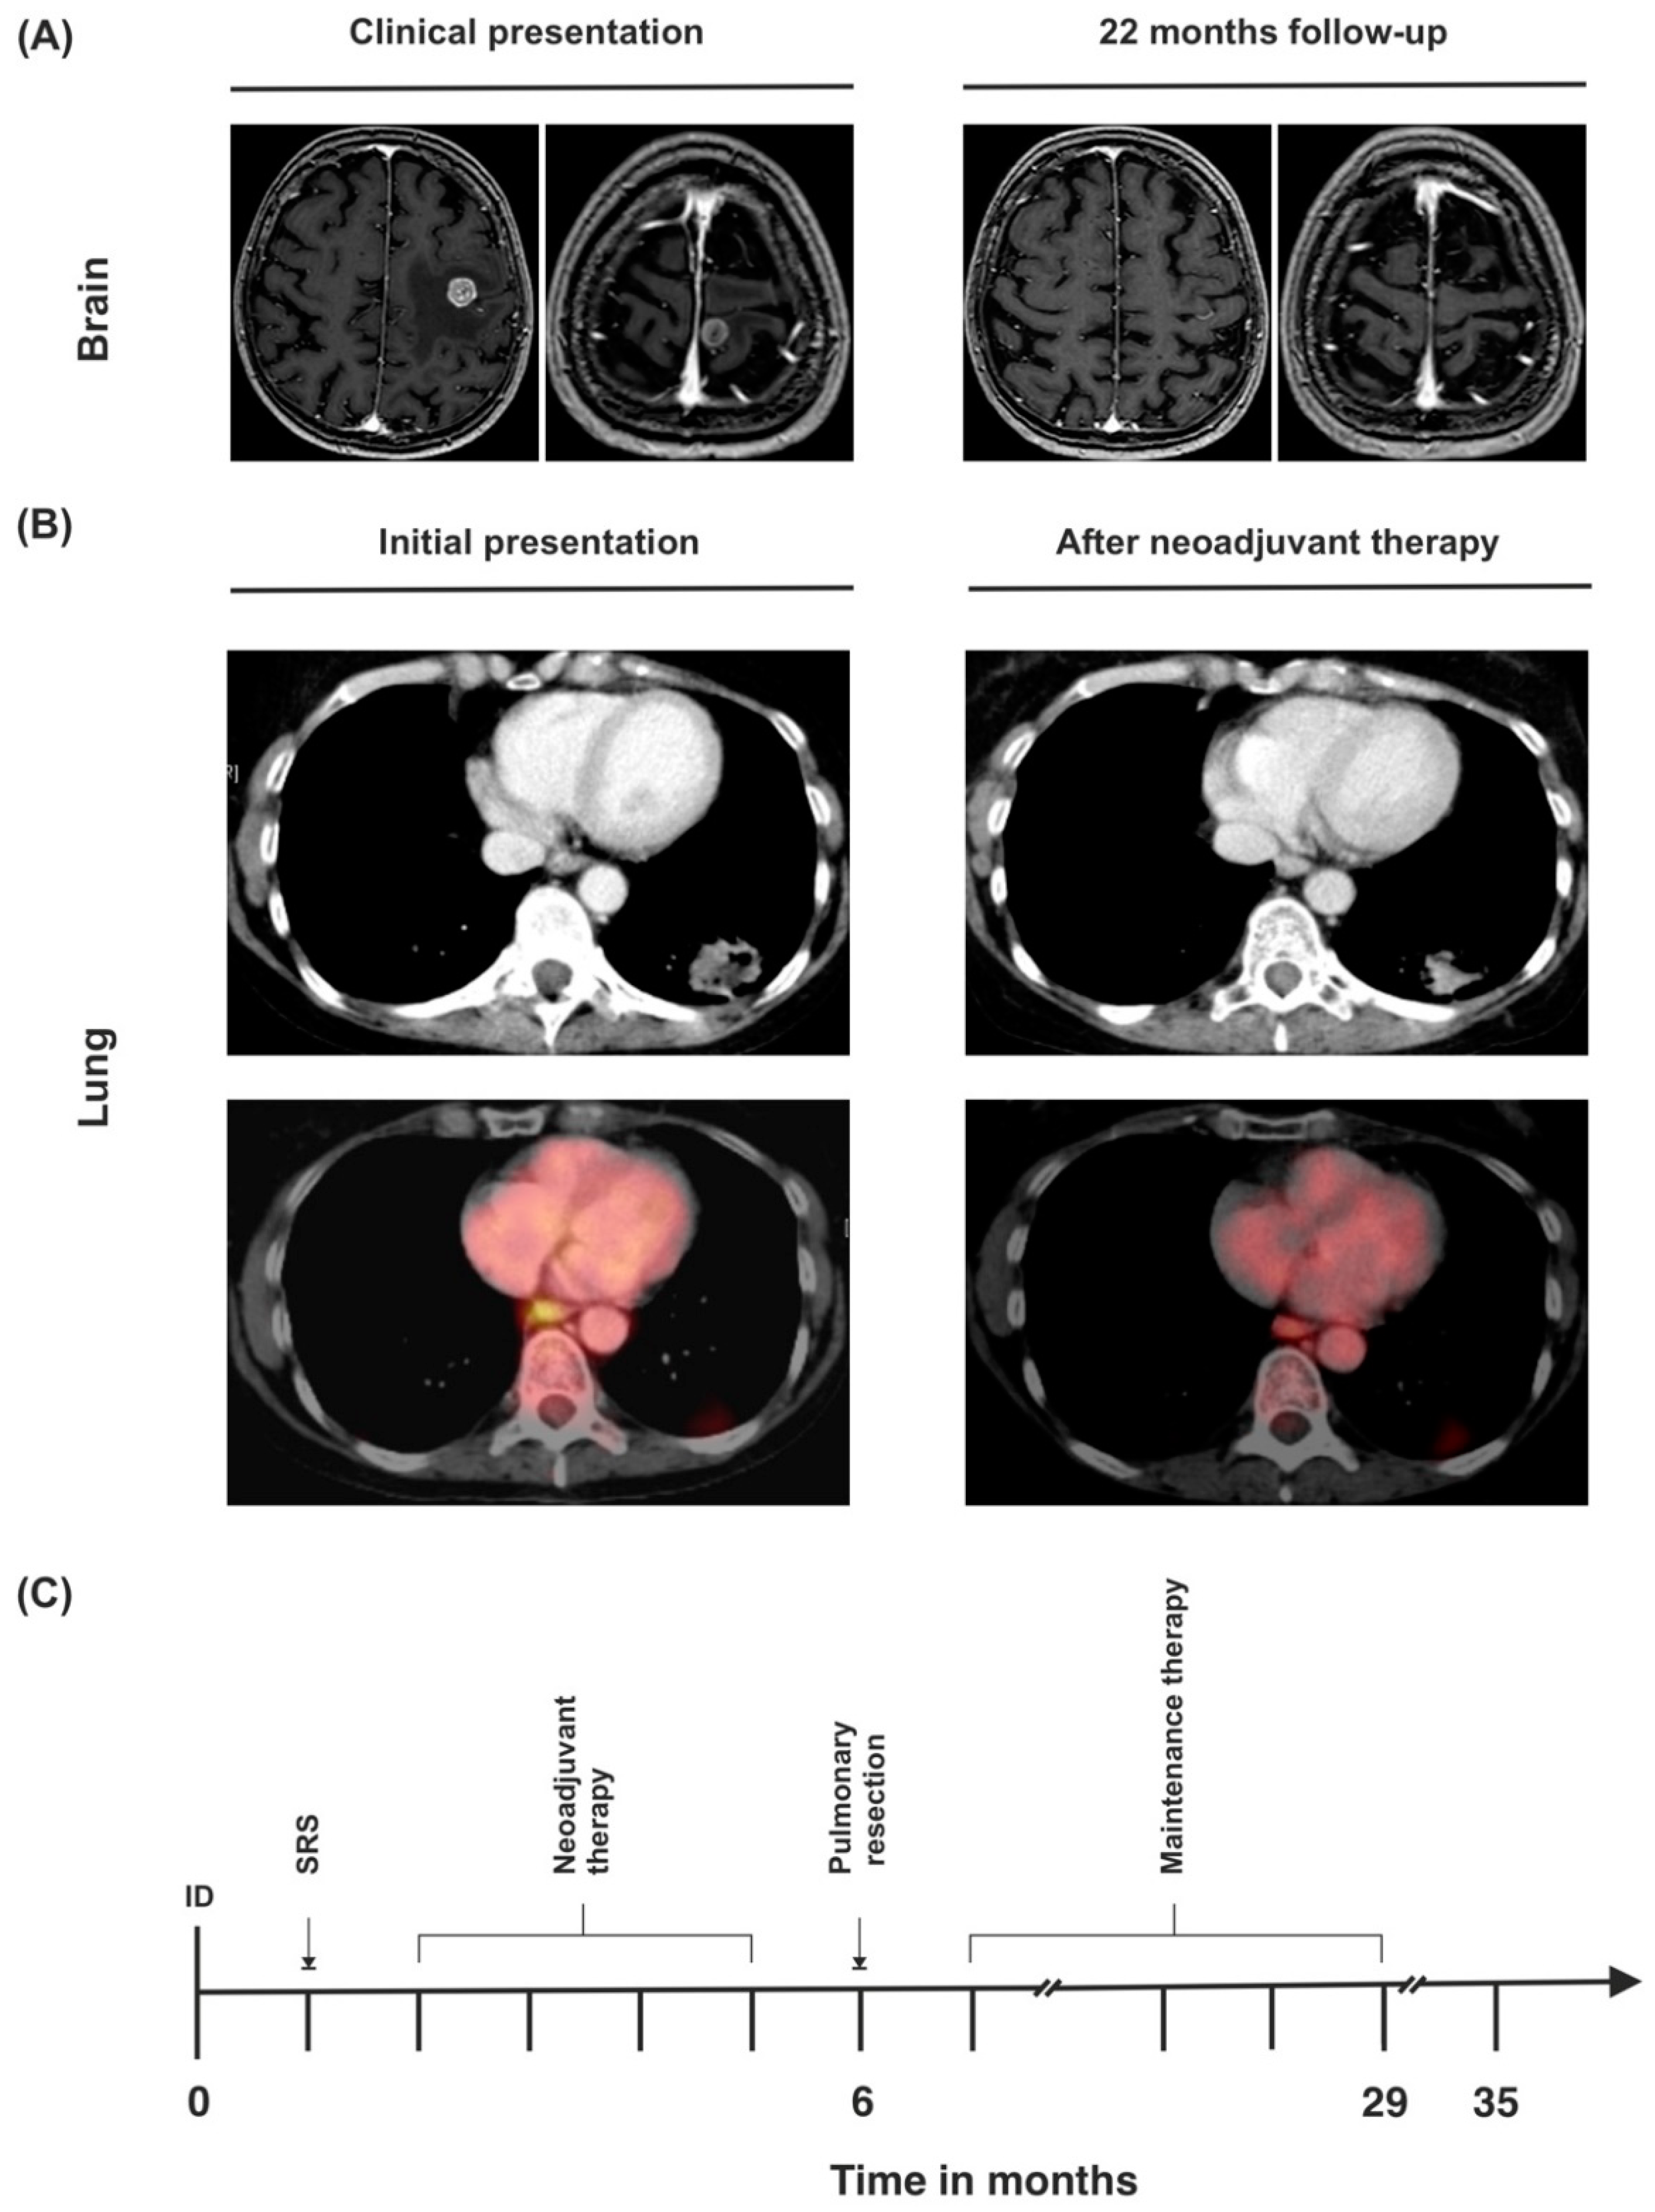

3.3. Case 3

| Treatment of BM | Neurosurgery and SRS | Neurosurgery and SRS | SRS |

| BM radiation dose | 21 Gy | Synchronous BM: 21 Gy, metachronous BM: 20 Gy | 19 Gy |

| Neoadjuvant therapy | Cisplatin (75 mg/m2), pemetrexed (500 mg/m2), and pembrolizumab (200 mg) | Cisplatin (75 mg/m2), pemetrexed (500 mg/m2), and pembrolizumab (200 mg) (+2 cycles of pembrolizumab as maintenance therapy) | Cisplatin (75 mg/m2), pemetrexed (500 mg/m2), and pembrolizumab (200 mg) |

| Pulmonary resection | Posterolateral thoracotomy, subsegment S1-resection, right lower lobe resection, systematic lymph node dissection | Posterolateral thoracotomy, extrapleural extended upper lobectomy, wedge resections (S1, S5, S6), systematic lymph node dissection | Posterolateral thoracotomy, extended left lower lobe resection, wedge resection S1, systematic lymph node dissection |

| Tumor stage after lung resection | ypT0 ypN0 (0/42), L0, V0, R0, Gx, pM1b (BRA), UICC IVA | ypT2b ypN0 (0/22), L0, V0, Pn0, R0, Gx, pM1b (BRA), UICC IVA | ypT2a ypN3 (5/23), L1, V1, Pn0, R0, cM1c (BRA), UICC IVB |

| Maintenance therapy | 200 mg per cycle (ongoing) | 200 mg per cycle (discontinued after 2 cycles because of progressive disease) | 200 mg per cycle (finished after 24 months) |

| Current Karnofsky performance index | 100% | 0% | 100% |